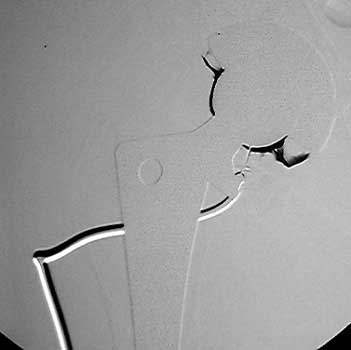

Arthrographic evidence of looseningcontrast enters

abnormally widened interface Gruen zone 1 and 2